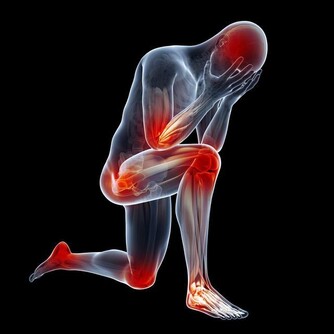

還需了解一點,就是三叉神經痛,發作的大多都比較突然,停止得也比較突然,而引起的疼痛感覺也是多樣化的,但大多都不能讓人忍受,即便只是持續很短時間,也會讓人忍受不住。

三叉神經痛,不是一個應該被忽視的疾病,40歲以後的人群,應該早做預防,畢竟,三叉神經痛發生後,帶來的痛苦也是很煎熬,不僅僅是引起牙痛,還可能出現臉痛、偏頭痛,被疼痛折磨的人,也是如坐針氈,希望你能引起重視。